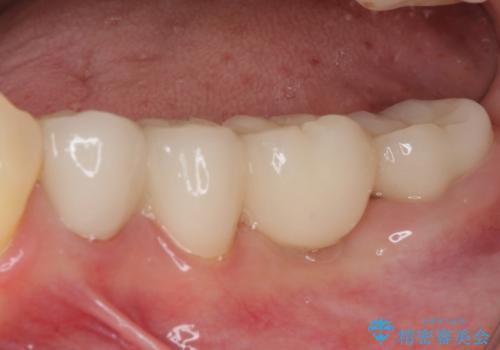

治療開始の日に欠損部も含めて仮歯が装着され、今までの不具合や不快感があっという間に改善されました。

抜歯部位の治癒を待つために時間がかかりましたが、来院回数は数回で済み、患者様には大変満足していただきました。